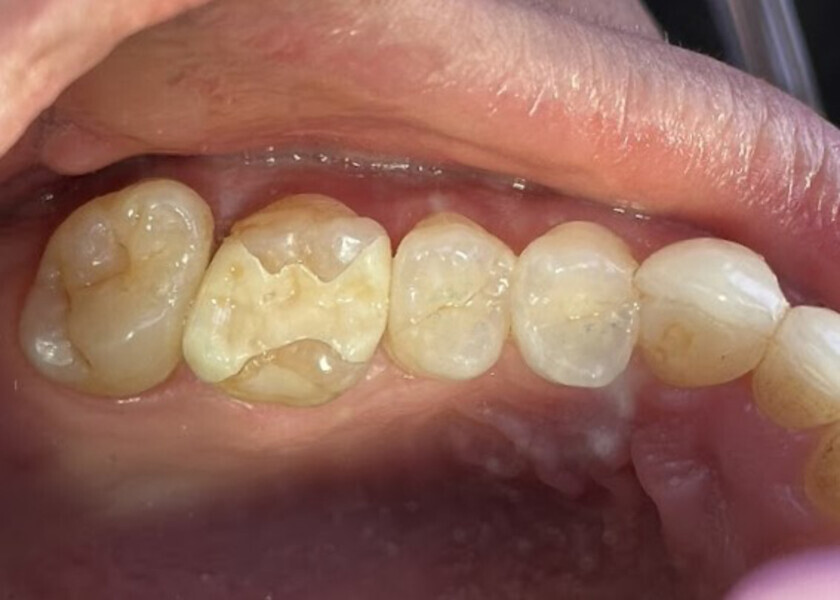

A 23-year-old female patient presented with cold sensitivity of the teeth in the maxillary right posterior sextant. Examination noted old composite fillings in the molars and premolars and recurrent caries on each tooth (Fig. 19). A bitewing radiograph was taken to evaluate the extent of the recurrent caries and the dimensions of the composite restorations (Fig. 20). Owing to the dimensions of the restorations and caries, inlay and onlay restorations were suggested to restore the teeth and preserve tooth structure as an alternative to complete crowns. The patient’s questions were answered, and she agreed to the proposed treatment. She was informed that the treatment could be completed in a single appointment utilising 3D printing for restoration fabrication. Time in the schedule permitted treatment to be performed during that same appointment. Our intent is to provide conservative restoration with superior accuracy and definition compared with milling, as well as better predictability and mechanical properties compared with direct resin composite restorations.

Fig. 19: Clinical view of the old composite restorations with recurrent caries on the molars and premolars.